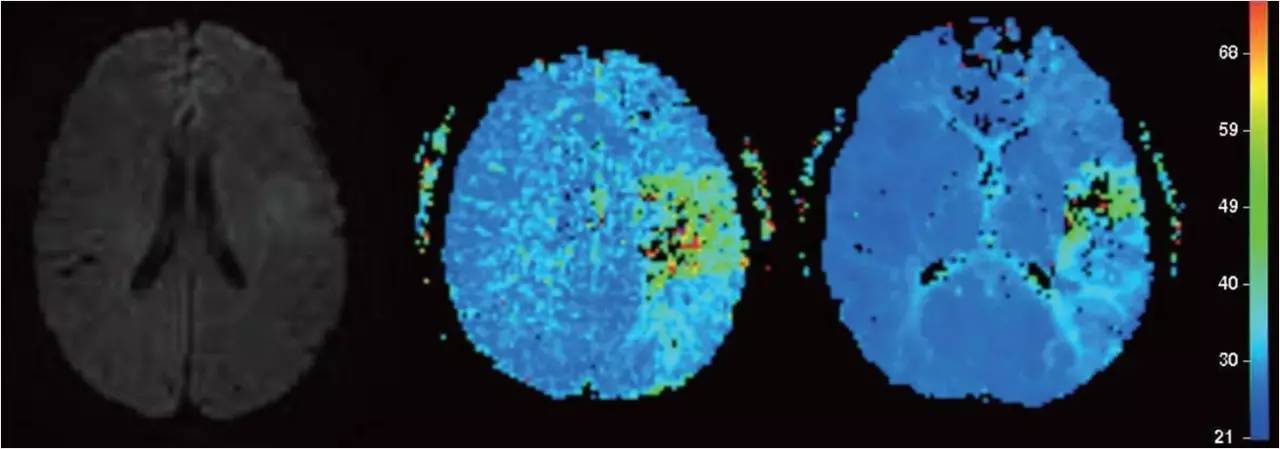

文献回顾

取栓治疗何去何从?

mechanical embolectomy in cases of troke due to infective endocarditis manifesting with major neurologic deficits is a subject of controversy and needs additional clinical experience and evaluation in a randomized trials.

取栓治疗对脑梗死所致严重神经功能障碍的疗效需要:

#进一步的临床经验积累

#高质量的随机对照研究